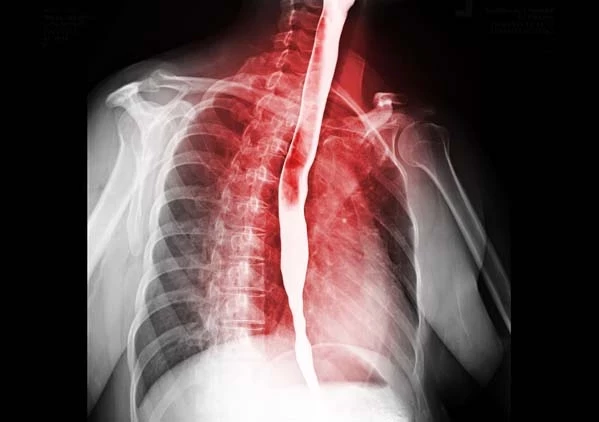

Bu başarı, Andrew’un artık ameliyat edilebileceği anlamına geliyordu; ‘özofajektomi’ yapılacaktı yani sağ akciğeri söndürülecek ve yemek borusunun yaklaşık 15 santimetrelik kısmı kesilip atılacaktı.

Sekiz saat süren ve oldukça invaziv olan bu ameliyat, vücudunda göğüs kafesinden göbeğinin altına ve sırtına kadar uzanan devasa bir iz bıraktı. İyileşme süreci çok zordu ama yapılan son tomografi taraması, kanserden eser kalmadığını gösterdi.